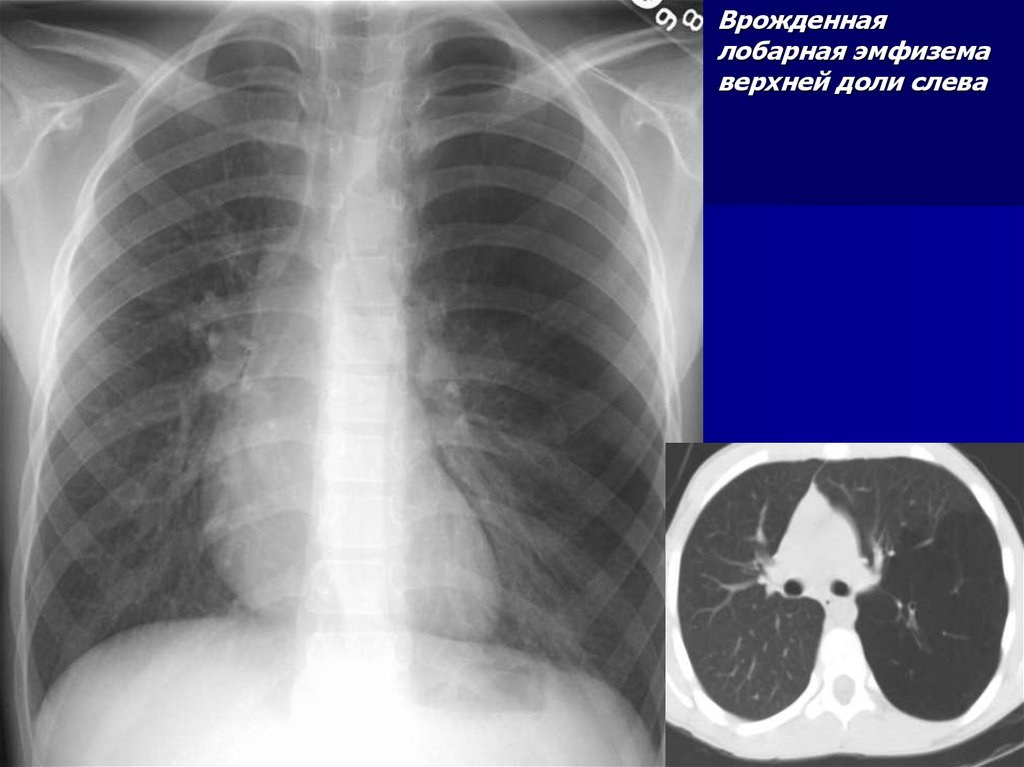

46.

Врожденная

лобарная эмфизема

верхней доли слева